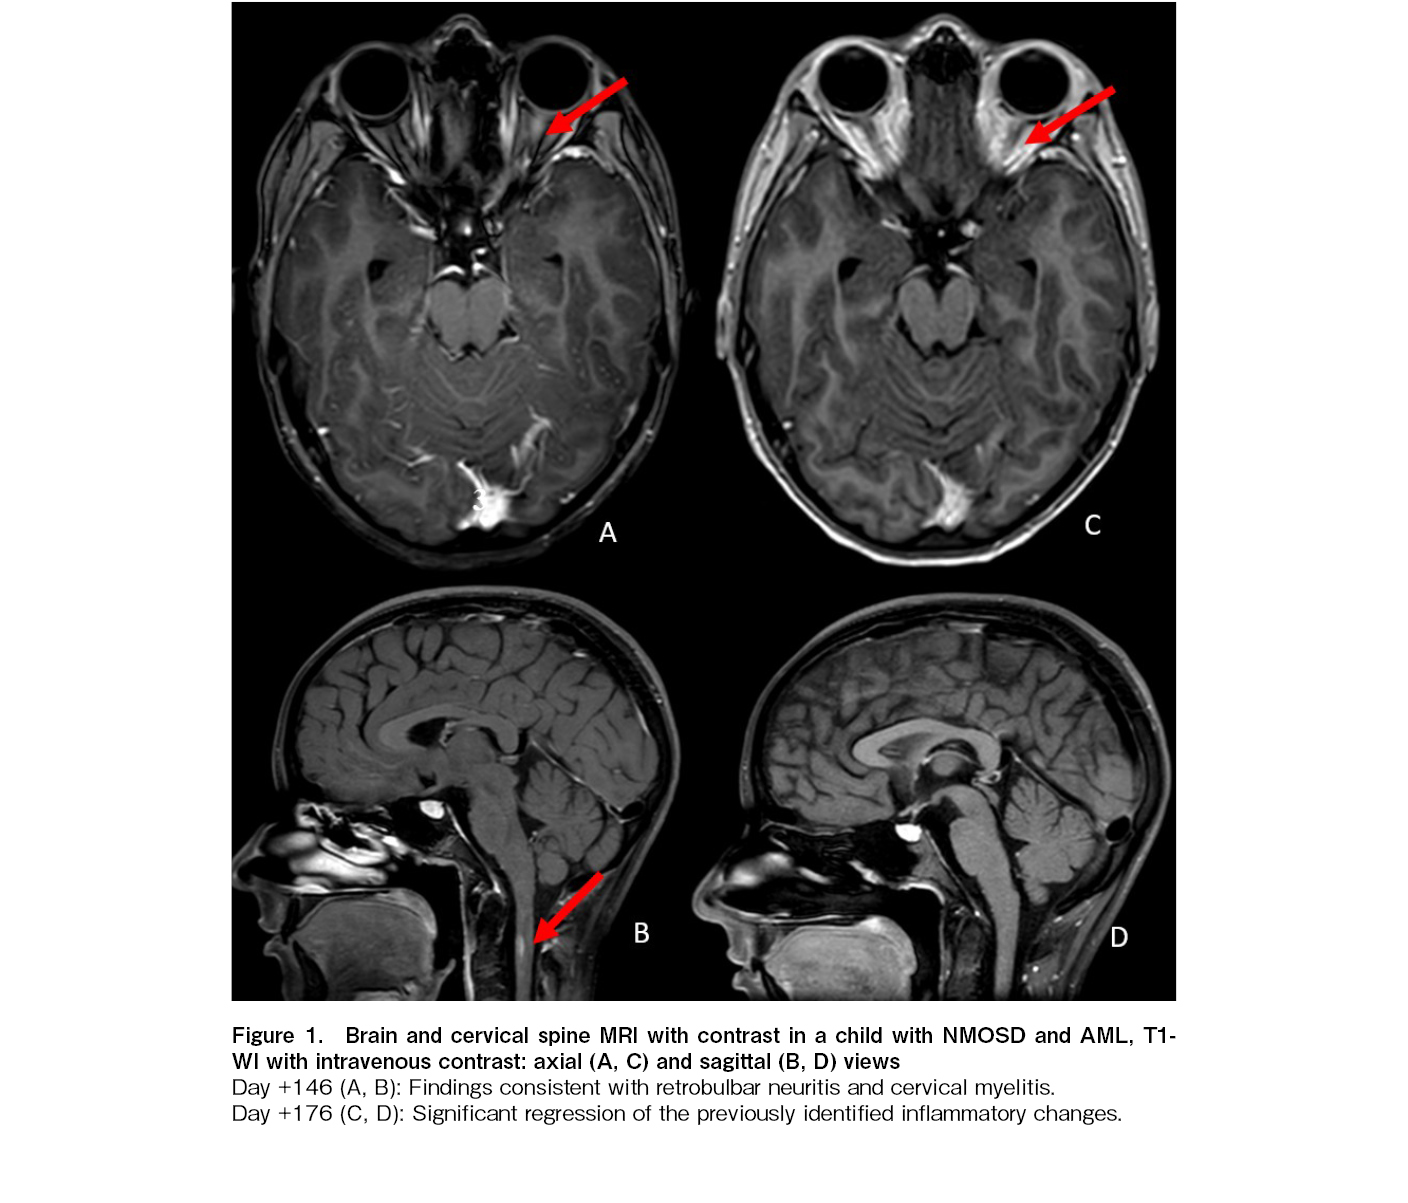

On day+145 after the second HSCT, the patient reported pain in the left orbit upon eye movement. Concurrently, she developed arthralgia and exhibited lichenoid changes of the oral mucosa, findings highly characteristic of chronic GVHD. Ophthalmological examination revealed unilateral papilledema. A contrast-enhanced MRI of the brain showed findings consistent with isolated retrobulbar neuritis of the left optic nerve and a focal myelitic lesion at the C2 level. No other demyelinating lesions were detected on spinal cord MRI. Cerebrospinal fluid (CSF) analysis was negative for viral pathogens [cytomegalovirus (CMV), epstein-barr virus (EBV), human herpesvirus 6 (HHV6), varicella-zoster virus (VZV), herpes simplex virus (HSV1/2), BK polyomavirus (BK), JC polyomavirus (JCV), Parvovirus B19] and blast cells; a mild elevation in CSF protein was noted. AQP4-IgG antibodies and MOG-IgG were not detected in the serum or CSF. A diagnosis of seronegative NMOSD, likely of alloimmune origin, was established.

The patient received sequential therapy with four sessions of PLEX, two doses of rituximab (375 mg/m2, administered two weeks apart), and one pulse of cyclophosphamide (750 mg/m2). Treatment response was evaluated after this induction phase, which led to a significant improvement and complete resolution of the orbital pain. Maintenance therapy consisted of six monthly courses of intravenous immunoglobulin (IVIG) at 2 g/kg per course. A follow-up MRI on day+176 demonstrated a partial reduction of inflammatory changes in the optic nerve and complete resolution of the spinal cord lesion (Figure 1). The finding paralleled by the complete resolution of arthralgia and significant improvement in oral lichenoid manifestations.